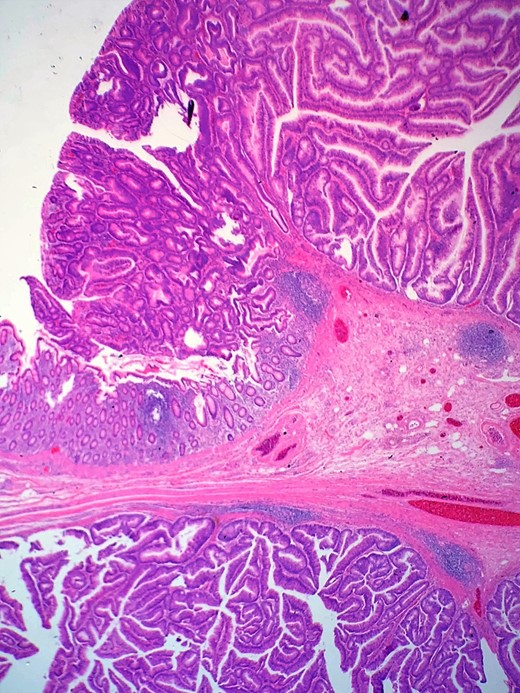

Definitive histological examination showed perforated appendix involved by moderately differentiated mucinous adenocarcinoma (Fig. 5), arising in the background of diffuse tubulovillous adenoma with extensive high-grade dysplasia and showed cellular mucin within the periappendiceal soft tissue (Figs 6 and 7). Proximal cecal mucosal margin and mesenteric margin uninvolved by carcinoma and four periappendicular lymph node was negative for metastatic carcinoma and pathological stage aided for pT4a, pN0. The post-operative course was uneventful. The tumor was staged as T4N0M0 (Modified Astler Coller B3). Patient was referred for oncology and for multidrug adjuvant chemotherapy of 5-fluorouracil, lecovorin and oxalipatin (FOLFOX) was given. Patient was asymptomatic during the 2 weeks, 3 months and 6 months follow up.

Shows transition of normal cecal mucosa to high-grade tubulovillous adenoma at the appendiceal orifice.